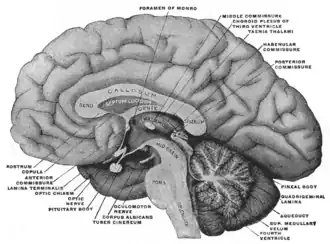

Головной мозг человека. Разрез по медианной сагиттальной плоскости. Мезиальный вид. | |